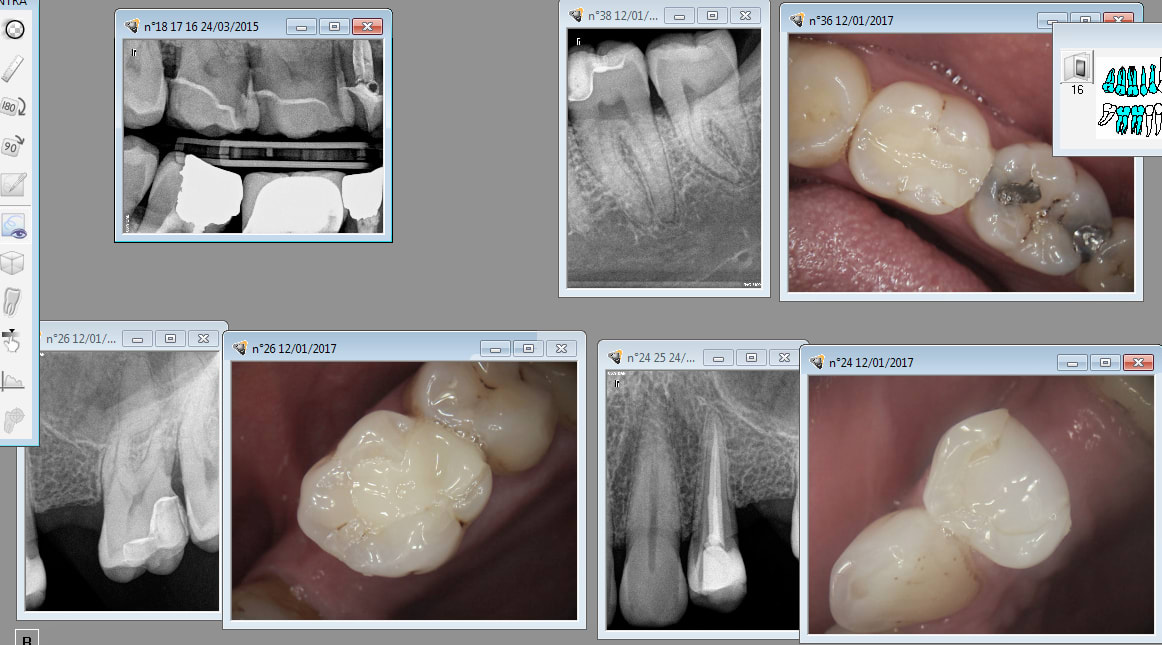

Ca c'est un copain. Onlays cerec faits en 2007 pour la modique somme de 121,08 euros ( ED)

150 euros en tout. Tarif d'ami. Mais quand tu fait pas un tarif d'ami tu n'en fais pas. -)